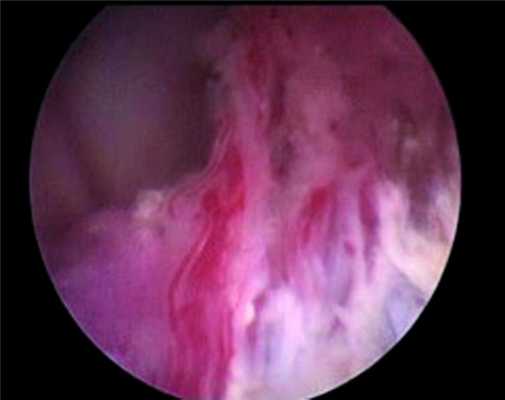

Новообразование занимало большую часть тела правого бокового желудочка, исходным местом роста являлось сосудистое сплетение. Проведена инспекция тела правого бокового желудочка при помощи эндоскопа 30°, выявившая длинную сосудистую ножку, исходящую из задней хориоидальной артерии (рис. 4),

Рисунок 4. Питающая опухоль сосудистая ножка — вид через оптику эндоскопа 30°. которая прокоагулирована и отсечена при помощи микроножниц.

При эндоскопической инспекции височного рога обнаружены дополнительные артерии, подходящие к опухоли, которые также были прокоагулированы и отсечены при помощи микроножниц. После этого остаточные части опухоли, располагавшиеся в задней части правого бокового желудочка, были легко удалены. Опухоль не инфильтрировала окружающую мозговую ткань, и при эндоскопической инспекции желудочковой системы остатков опухоли обнаружено не было. Контроль гемостаза и наличия остатков опухоли произведен с помощью эндоскопической оптики 0, 30° (рис. 5).

Рисунок 5. Ложе удаленной опухоли — контроль гемостаза и радикальности удаления (область сосудистого треугольника). Эндоскоп 0°.